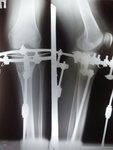

Рентген в 81 день с момента операции.

Здравствуйте, Соломея! По рентгену, у Вас всё отлично! В 90 дней возможно снятие аппаратов. Натаптывайте интенсивно ножки все эти дни, но без фанатизма(ведь когда я Вам говорю больше ходите- это значит, что при физ нагрузке быстрее разрастается костная ткань - вырабатывается, наступает сращение) лучше приехать и остаться у нас в клинике до снятия аппаратов. Один раз можно пожертвовать временем, расстоянием и средствами ради благополучия и отличного результата! Ножки мы исправляем один раз и навсегда!